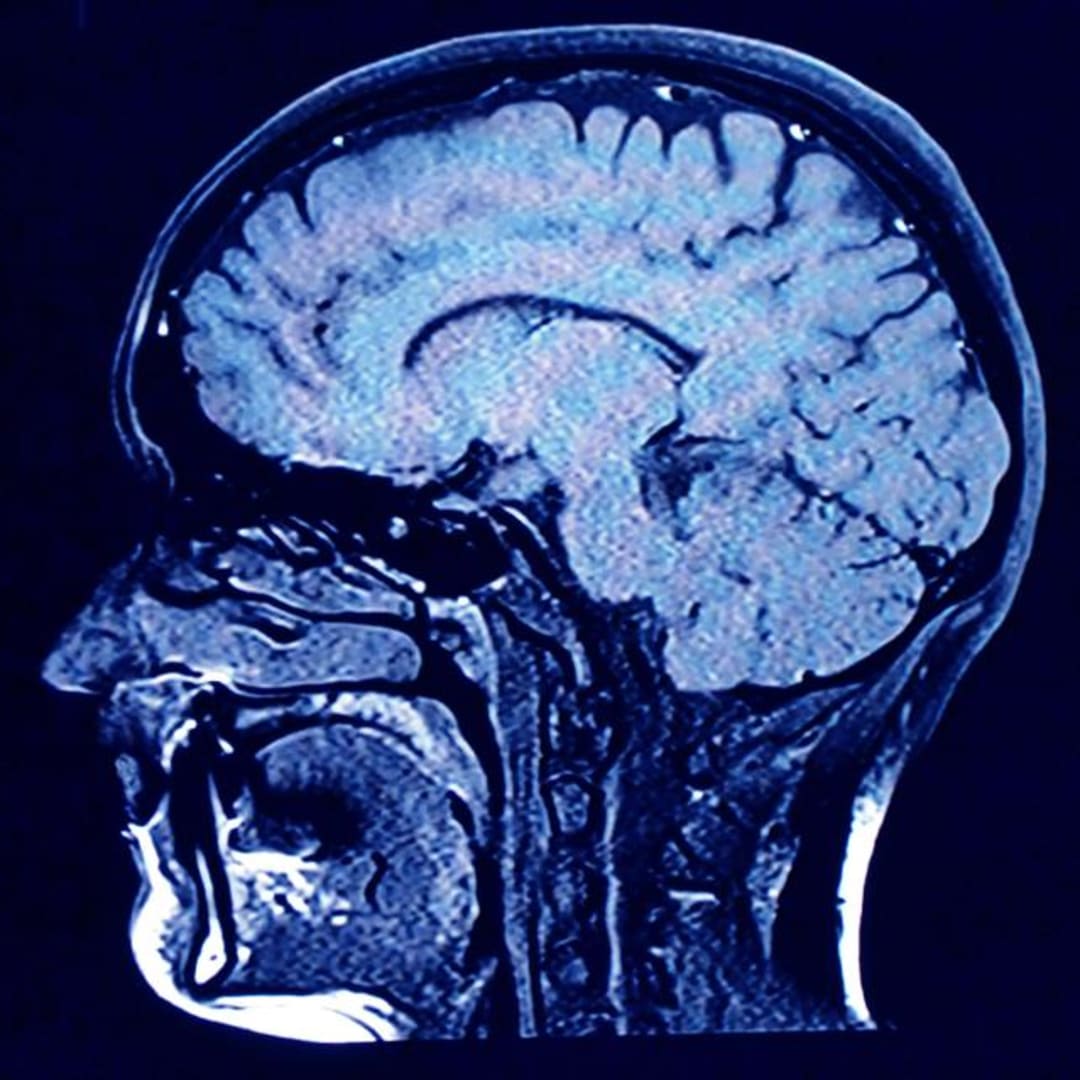

Mikroplastik Menumpuk dalam Otak Manusia: Ancaman Baru yang Mengkhawatirkan

Produksi plastik yang terus meningkat menyebabkan partikel-partikel kecil bernama mikroplastik terkumpul di mana-mana, termasuk di dalam tubuh manusia. Penelitian dari Universitas New Mexico menunjukkan bahwa mikroplastik lebih banyak ditemukan di otak dibandingkan dengan organ lainnya, seperti ginjal dan hati. Dalam sampel otak manusia, ditemukan 12 jenis polimer yang berbeda, dan rata-rata otak bisa mengandung sekitar 4.800 mikrogram mikroplastik per gram. Jumlah mikroplastik di otak juga meningkat pesat dalam delapan tahun terakhir.

Para ilmuwan menduga mikroplastik masuk ke dalam tubuh kita melalui makanan, terutama daging, yang terkontaminasi oleh plastik. Meskipun mereka belum tahu apakah mikroplastik berbahaya bagi kesehatan, mereka menemukan bahwa otak penderita demensia memiliki lebih banyak mikroplastik. Penelitian lebih lanjut diperlukan untuk memahami dampak mikroplastik pada kesehatan manusia, tetapi para peneliti berharap temuan ini dapat meningkatkan kesadaran masyarakat tentang keberadaan plastik di dalam otak mereka.